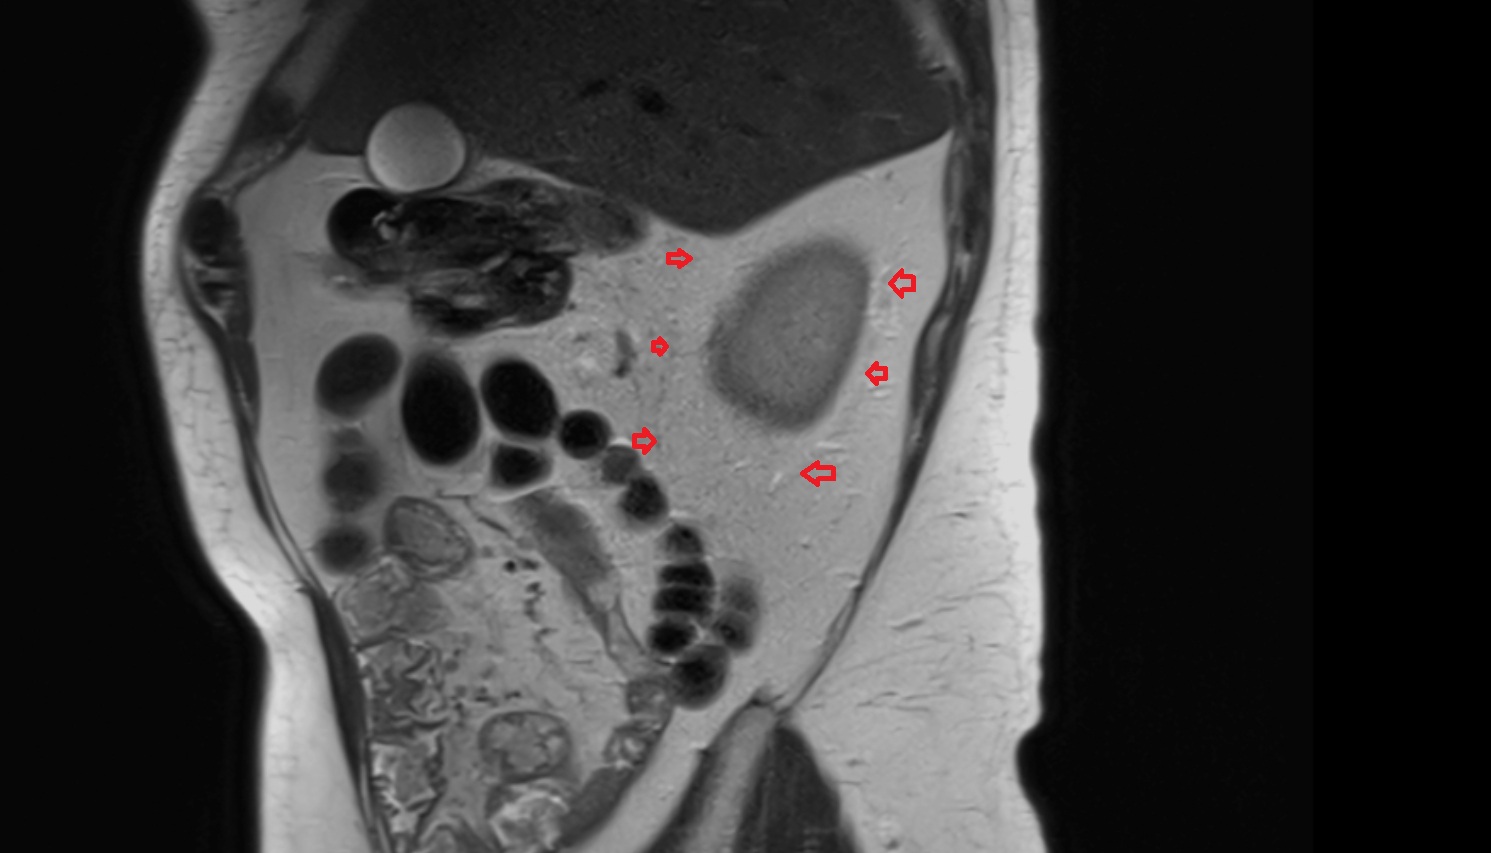

- Placenta

- Uterus (pregnancy)

- Amniotic fluid

- Umbilical cord

- Urinary Bladder in Pregnancy

- Cervix in Pregnancy

- Vagina in Pregnancy

- Fundus of uterus in pregnancy

- Fetal brain

- Fetal kidneys